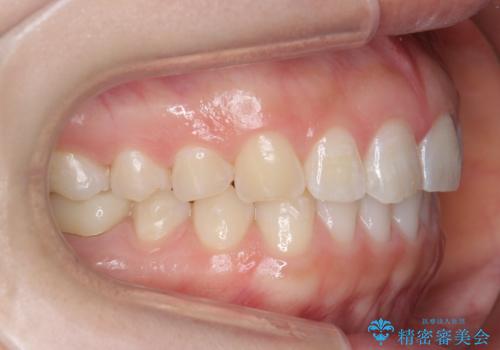

- 下の前歯のがたつきを治したいとのことでした。

上の前歯のちょっとしたねじれも治療しています。

軽度だったため、部分矯正のコースで短期間で治療しました。

下の歯並びを並べるため、わずかに歯を削合しています。

そうしないと、前に出て上の前歯に強く当たってしまうためです。また、後戻りを防ぐ効果もあります。

年齢を重ねてくると、下の前歯が目立つようになるので治療しておくと若々しい印象を保つことができます。